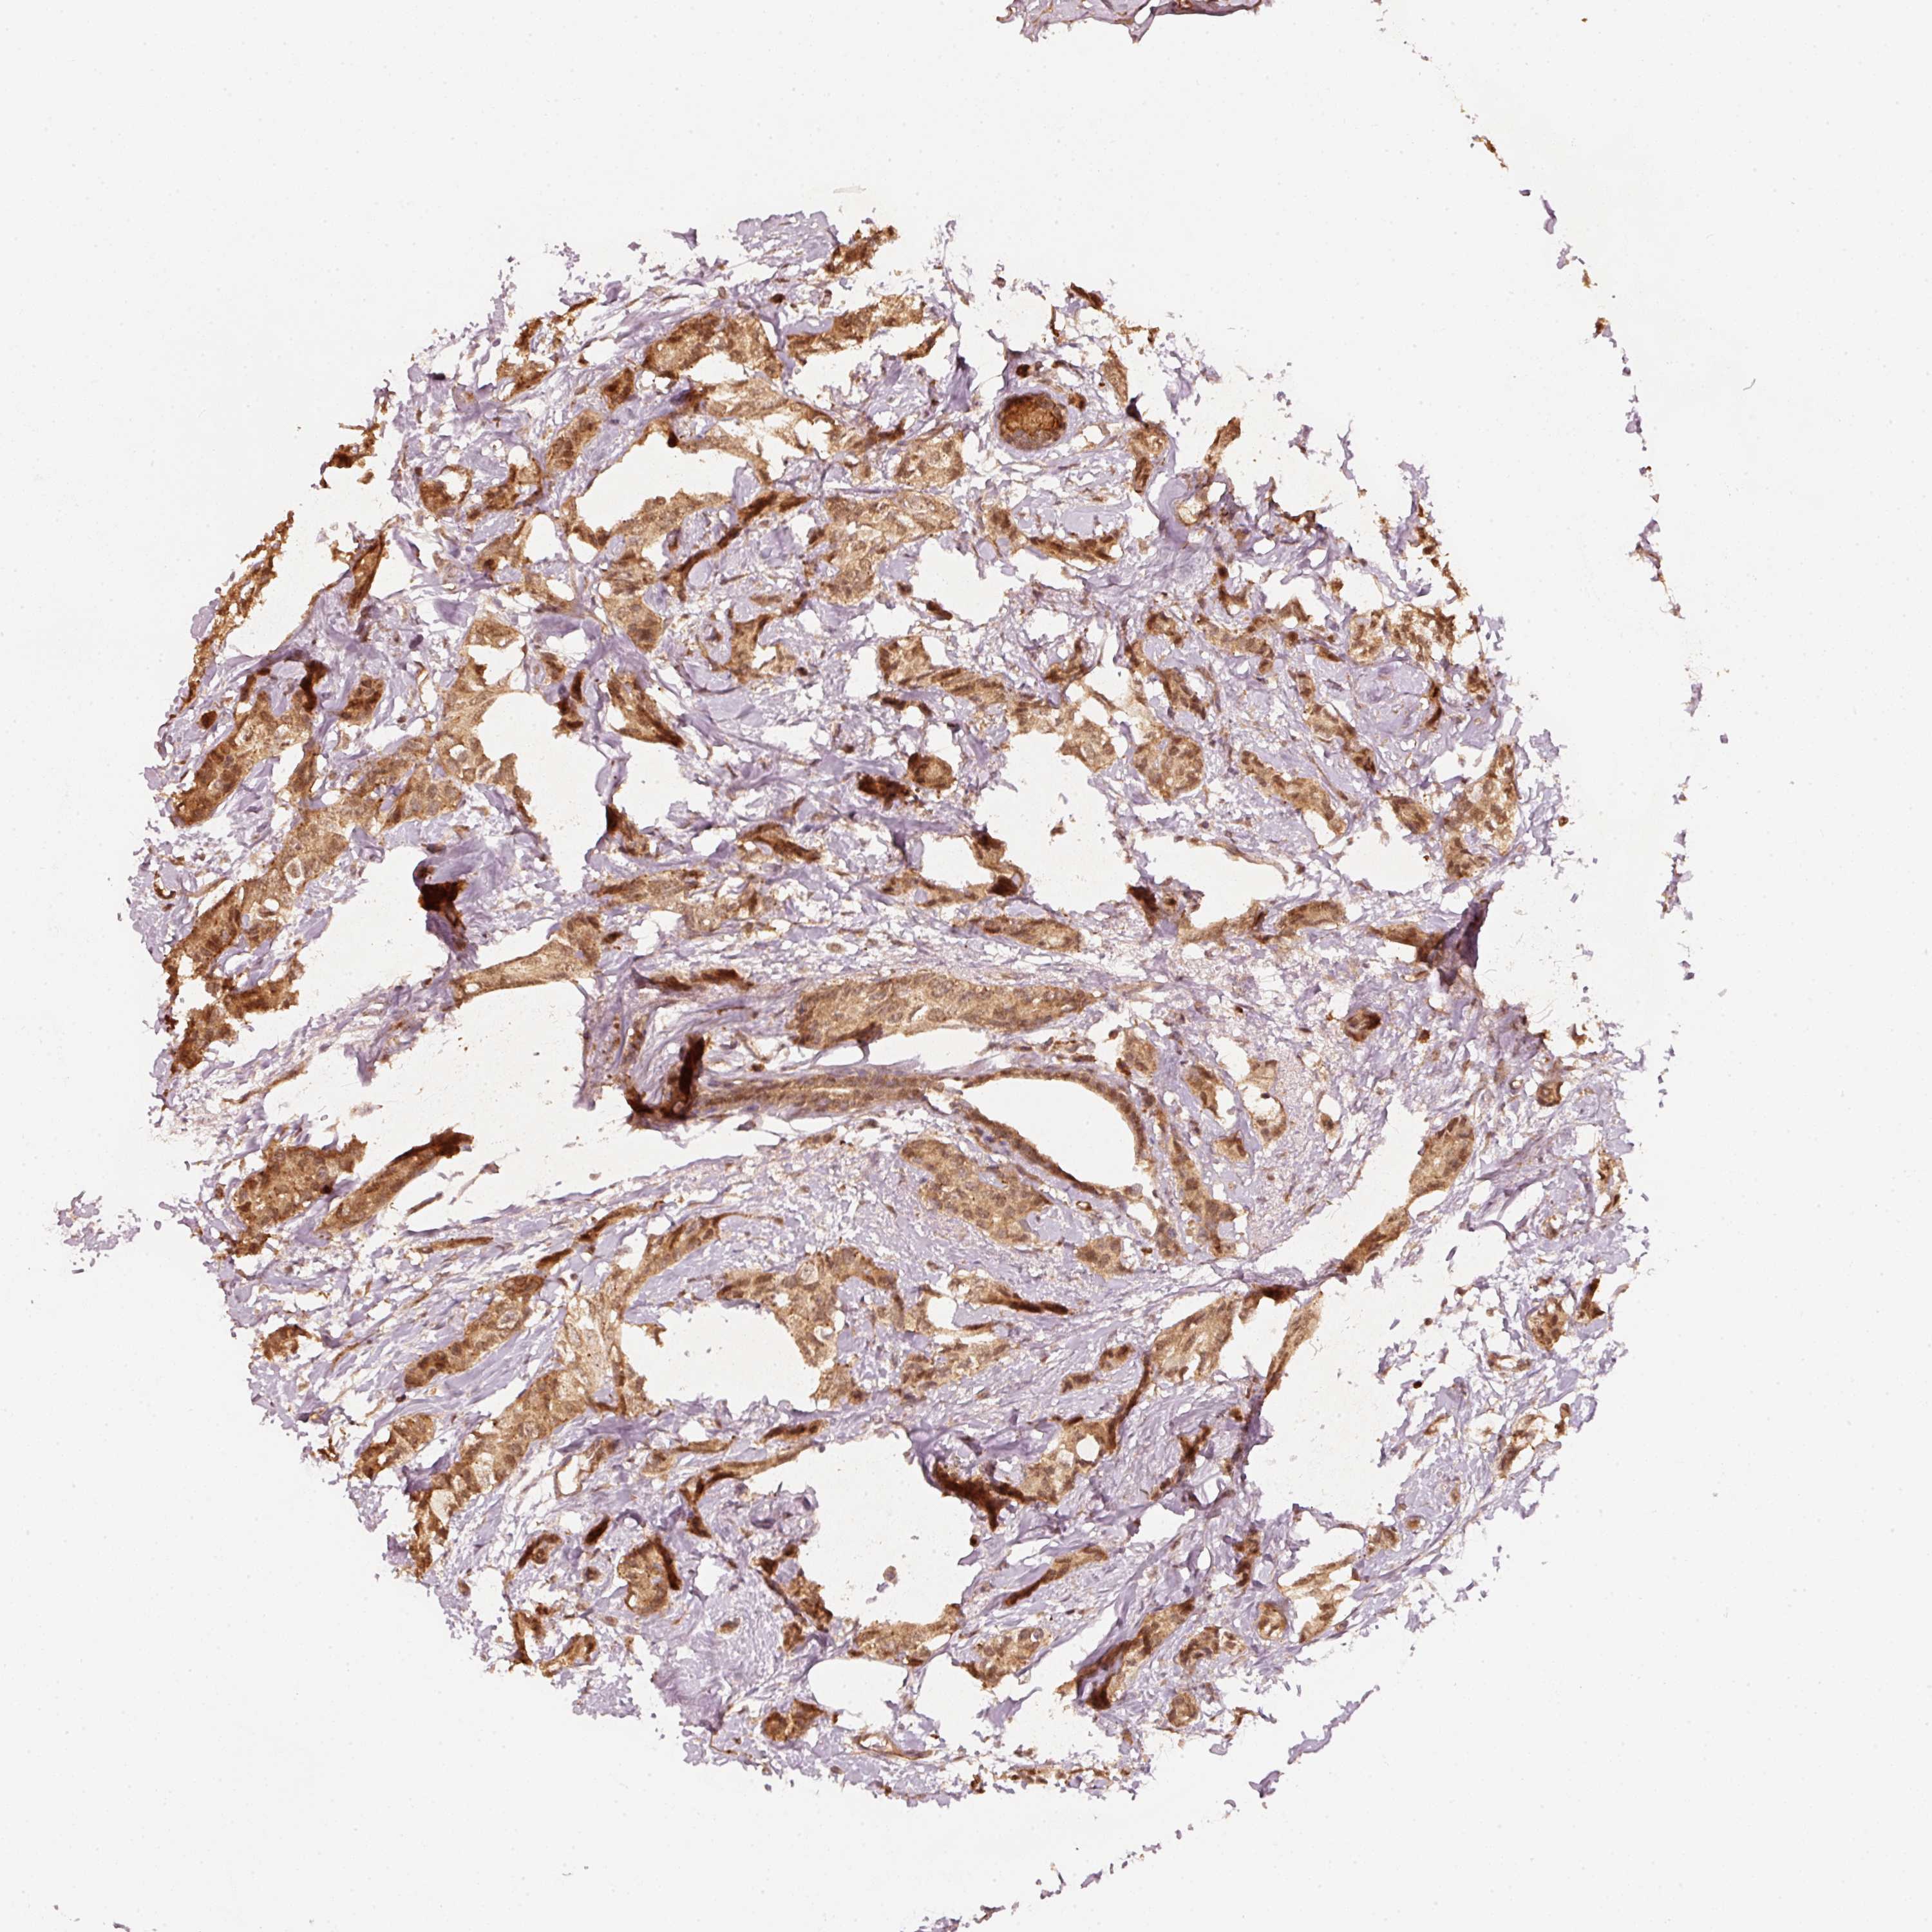

BRCA TCGA BRCA VALIDATION PROTEIN EXPRESSION

ANTIBODIES

AND

VALIDATION